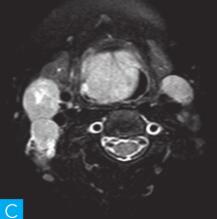

喉咽部MRI检查:病人采取仰卧位,横断位扫描为主,包括T1WI、T2WI及T2WI脂肪抑制序列,扫描范围自鼻咽部至喉咽以下,扫描层厚为3.5mm、层间隔0.35mm,矩阵512×512;辅以冠状位T2WI,矢状位T2WI序列及脂肪抑制序列,平扫后行横断位、冠状位及矢状位的增强扫描,造影剂量0.2ml/kg。见图1。

图1 咽喉部MRI:A.喉咽部MR横断面平扫T1WI;B.喉咽部MR横断面T2WI;C.喉咽部MR横断面T2压脂;D.喉咽部MR横断面增强T1WI;E.喉咽部MR冠状面T2WI;F.咽喉部MR冠状面增强T1WI

MRI平扫可见右侧扁桃体较大的软组织肿块,T1WI呈稍低信号,T2WI呈稍高信号,信号较均匀,T2WI压脂序列上呈高信号,病变与右侧咽扁桃体及舌根部分界不清,左侧咽扁桃体肿大,口咽腔明显变形狭窄,病灶延伸至喉前庭;双侧锁骨上窝及颈血管鞘周围间隙内可见多发大小不等的肿大淋巴结,大部分肿大淋巴结信号较均匀,呈稍高信号,边界清楚,右侧颈部间隙内个别肿大淋巴结内见少量斑片状液化坏死区;增强扫描后下咽部病变及双侧颈部间隙内的肿大淋巴结均呈明显的较均匀强化,提示该两处占位病变的血供较为丰富,且可能为同源性病变,因此采取“一元论”诊断思维进行分析更为合理。

(1)发现病变与认证:扁桃体及颈部病变较为容易发现,主要是分析两方面:一是仔细观察咽部有无原发病变,原发病变的形态及信号;二是评价淋巴结的分布,淋巴结的信号及生长特点。本病例基本征象为扁桃体病变信号均匀,无坏死,颈部淋巴结分布广泛,信号均匀。

(2)定位诊断:对于本病例来说,发现两处病变,包括咽部和颈部。咽部的病变位于扁桃体,延伸至喉咽腔,口咽腔和梨状窝受压变窄。颈部的病变为多发淋巴结增大,淋巴结广泛分布于Ⅱ~Ⅴ区。

本病例的特点为右侧扁桃体肿块,病变边界较清楚,表面光滑,信号均匀。双侧颈部间隙内多发肿大淋巴结,淋巴结围绕颈动脉鞘,部分病变融合倾向,广泛分布于Ⅱ~Ⅴ区,增强后病变较明显强化。

该病例首先对病变进行定位,包括咽部的和颈部的。咽部的病变:病变位于扁桃体,延伸至喉咽腔,口咽腔和梨状窝受压变窄(引起异物感和吞咽困难的原因)。颈部的病变:多发淋巴结增大,淋巴结广泛分布于Ⅱ~Ⅴ区。扁桃体病变的信号特征:扁桃体病变表面光滑,提示黏膜完整,病变来源于黏膜下,病变信号均匀,无坏死,进一步支持病变来源于黏膜下。颈部淋巴结病变的特征:淋巴结分布广泛,信号均匀(可以初步排除结核和转移,后两者容易坏死),围绕颈动脉鞘,但是不侵犯颈动脉鞘(转移容易侵犯颈动脉鞘),部分淋巴结融合倾向(结核淋巴结增大,无融合倾向,而且容易坏死),病变中度强化,进一步支持颈部淋巴瘤的诊断。诊断原则:首先仔细观察咽部有无原发病变,原发病变的形态及信号,尤其黏膜是否完整。其次评价淋巴结的分布,淋巴结的信号及生长特点。